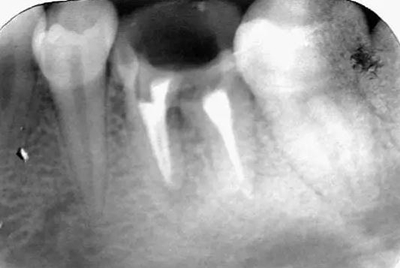

初診時X光片:根分歧炎癥懷疑有底穿,和患者交待病情和費用后開始治療。